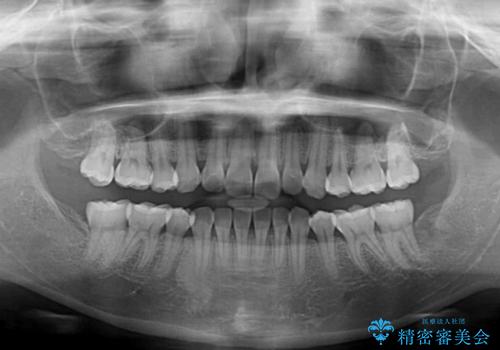

1. 抜歯矯正の軽度後戻りを解消 インビザライン矯正の治療前

2. 抜歯矯正の軽度後戻りを解消 インビザライン矯正の治療中

3. 抜歯矯正の軽度後戻りを解消 インビザライン矯正の治療後